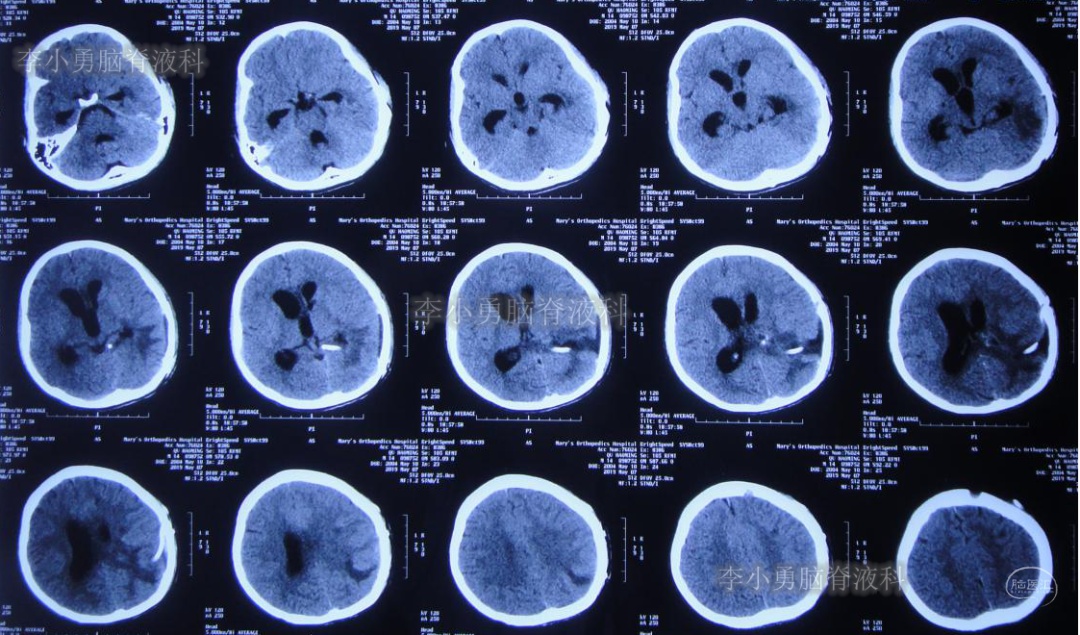

2019年3月26日患者突发头痛及呕吐,随后出现晕厥。急救车送至河南省周口市某医院。行头颅CT(图-1):脑室内出血,次日急诊给予行双侧脑室外引流术(图-2)(第一次的脑室外引流术)。

图-1:2019年3月26日头颅CT:脑室内出血

图-2:2019年3月27日头颅CT:双侧脑室外引流术后

双侧脑室外引流5天后即2019年3月31日,脑脊液颜色由血性明显变淡,意识转清,肢体活动良好,给予复查头颅CT(图-3):脑室不大,残留少许积血。

图-3:2019年3月31日头颅CT:残留少许积血